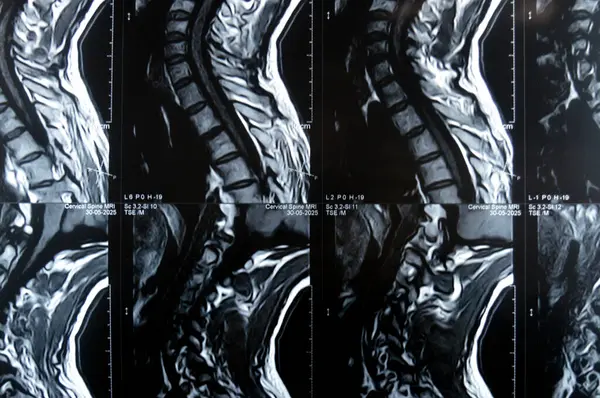

Servikal omurga MR 'ı boyun omurunda dejeneratif dejeneratif değişiklikler olduğunu gösteriyor. Dejeneratif disk lezyonları C3-C4, disk osteophyte kompleksi C4-C5, ve hafif C5-C6.